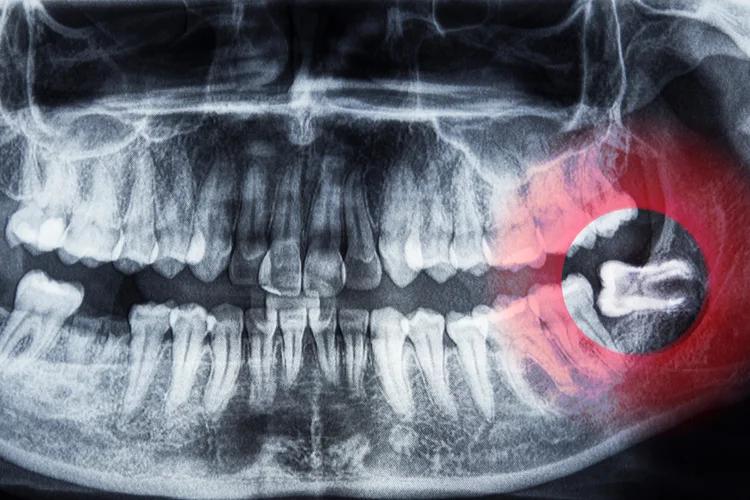

Assessing and diagnosing impacted or disrupted wisdom teeth typically involves a combination of clinical examination and imaging. This may include:

- Visual assessment to observe how the tooth is erupting and to examine the condition of the surrounding gums.

- Dental x-rays to determine the position of the tooth, the structure of the jawbone, and check its relationship to neighbouring teeth, especially if the tooth is not fully visible.

- Additional tests, such as pulp vitality testing, may be used to check the health of nearby teeth if an impacted tooth is suspected to be affecting them.